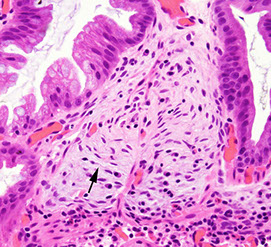

Gastric MALT lymphoma

LG B-cell lymphoma of Mucosa-Assoc Lymphoid Tissue (MALT); may be called extranodal marginal zone lymphoma

90% assoc c H pylori

30% plasmacytic differentiation

Micro: at low power, lamina propria expanded c small uniform cells, some of which have a "halo" around

- should start to assess muscularis mucosae, which usually have infiltrates of cancer cells

- the "lymphoepithelial" lesion (LEL) has lymphs scattered in residual gland epithelium (but not always there)

IHC: (+) CD20/79a, BCL2, IgM, can have plasmacytoid differentiation c Ig LC restriction; should assess for H pylori

Lymphoepithelial lesion